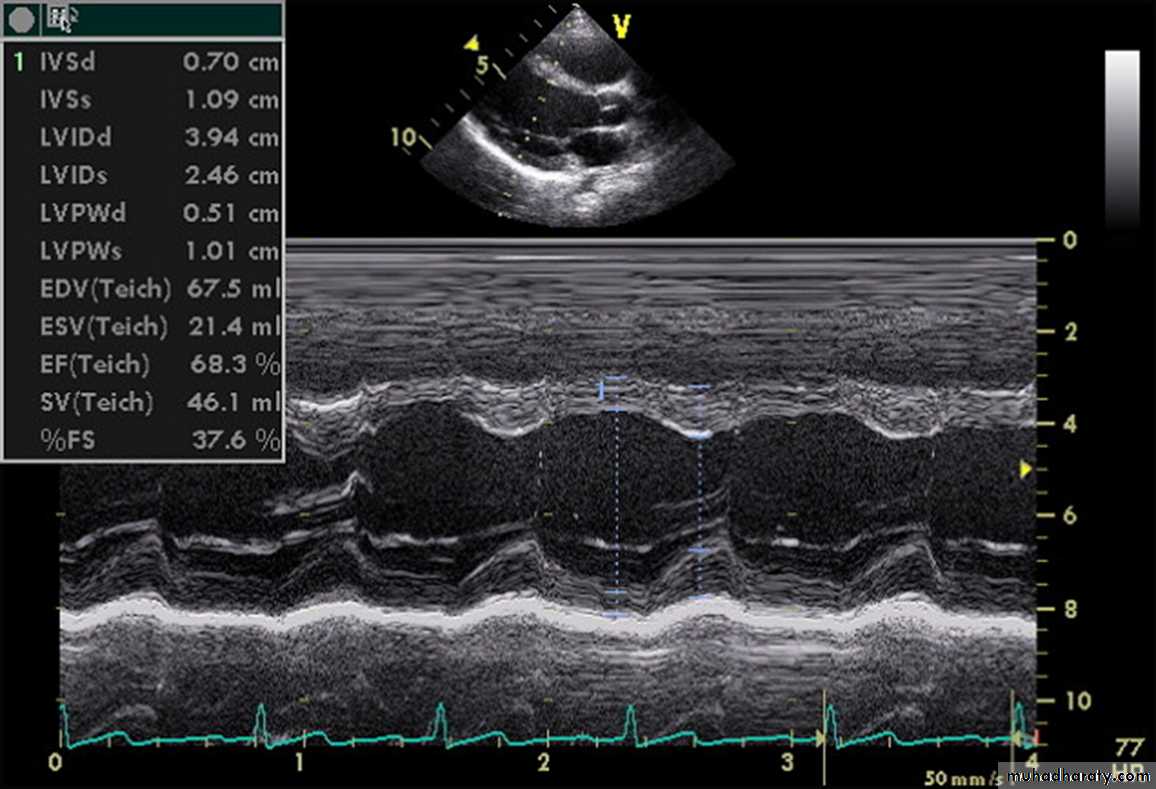

3-ECHOCARDIOGRAPHY

Echo studies may confirm enlargement of ventricular chambers and impaired LV systolic function (low fractional shortening or ejection fraction) as well as impaired diastolic function by the use of Doppler techniques.

A more important role of echo may be due to its ability to determine the cause of CHF.

Echo is also helpful in serial evaluation of the efficacy of therapy.